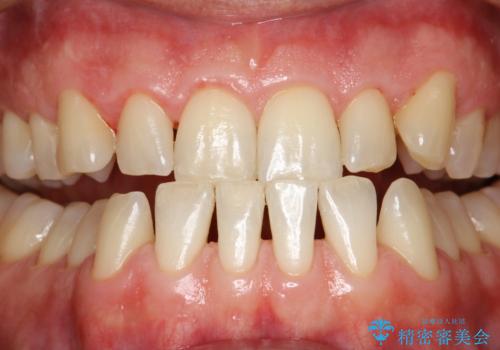

歯磨き中に血が出る PMTCで歯石除去

- 毎日の歯磨きの際に出血する。歯科でにクリーニンングをしばらくしていないとのことでした。PMTC60分コースを行いました。

歯磨きの際の出血は、歯肉炎や歯周病の症状とも言えます。歯周ポケットに歯周病菌が棲みつき、歯周病菌の出す毒素が歯茎に炎症を起こします。炎症が拡大し、歯周組織が破壊されたまま放置すると、最悪の場合、歯を支えている骨が溶かされ、歯がぐらぐらしてきます。

そのため重要なのが、毎日の歯磨きで可能な限り汚れを取り除くこと・定期的に歯科医院で歯周病の検査をしたり、歯石除去や歯茎の炎症を取り除くことです。